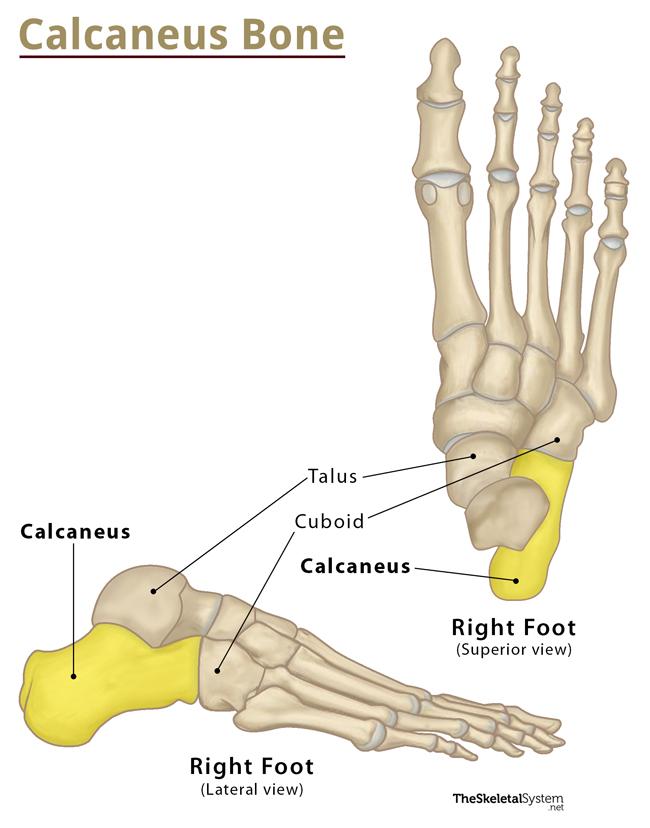

what is the calcaneus?

longest and strongest tarsal bone

what is an important landmark of the calcaneus?

sustentaculum tali

what is the sustentaculum tali?

shelf of calcaneus where tali sits on